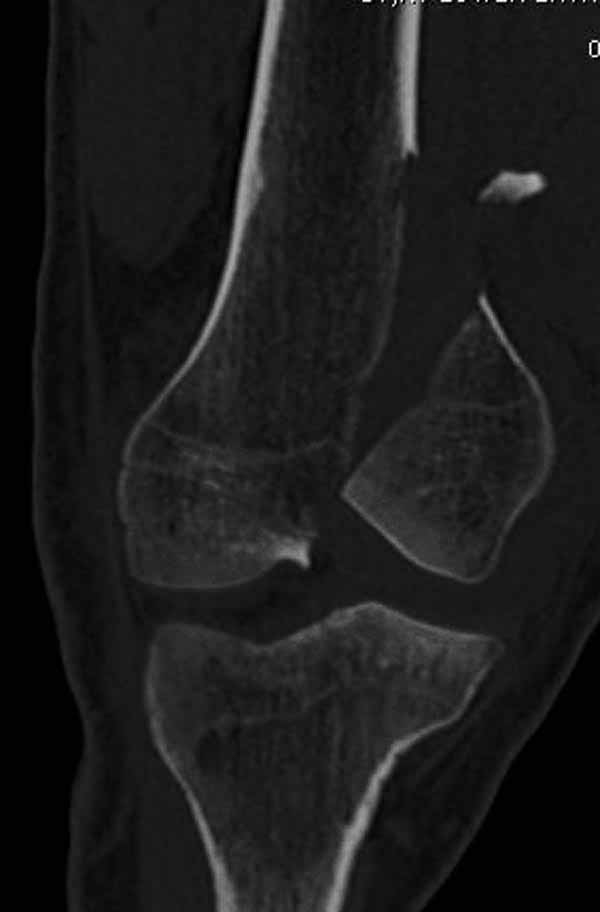

И не обратите, коллега, пока не сделаете четкие анфасные снимки (лучше с дистракцией) где будет четко визуализироваться малоберцовая кость. Думается, что и КТ здесь будет уместно, дабы не пропустить возможное флексионное повреждение (перелом Hoffa).

А теперь по поводу лечения перелома. Среди всех чрез/меж-мыщелковых переломов в 38% сопровождются переломом в корональной плоскости, т.е перелом Hoffa. Nork et al, J Orthop Trauma, 87:564, 2005.

Однако в случае, представленном Константином Никитиным, не может быть применён ни ретроградный ни антеградный остеосинтез. Причина - нереально выполнить вышеуказанные необходимые требования, касающиеся дистальных блокирующих винтов. Из-за низкого перелома латерального мыщелка (перелом Hoffa) невозможно через него провести хотя бы 2 блокирующих винта, поскольку линия перелома мыщелка расположена либо на уровне верхушки межмыщелковой ямки либо незначительно проксимальнее. Поэтому авторам, с моей точки зрения, необходимо прислушаться к рекомендациям Джолдаса.